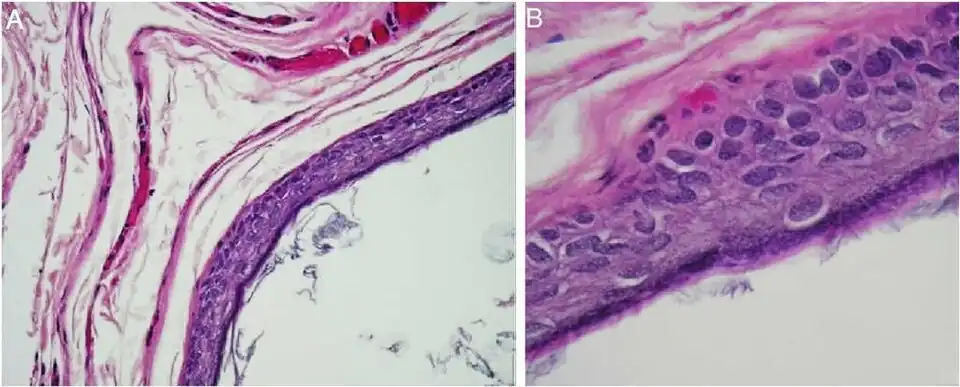

Histopathology, showing a keratinizing stratified squamous epithelium, and a lumen containing keratin flakes

Histopathology, showing a keratinizing stratified squamous epithelium, and a lumen containing keratin flakes -

Histopathology showing epithelium and lamellated keratin (left)

Histopathology showing epithelium and lamellated keratin (left)